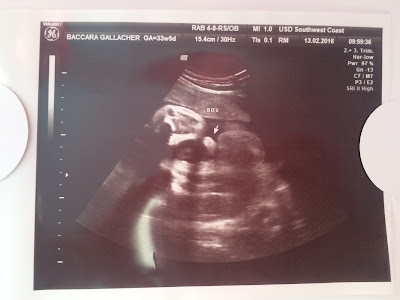

OUR 4D SCAN PHOTOS

As promised I thought I'd share the rest of the scan photos from our 4D Growth Scan. By NHS dates I was 33 weeks and 5 days on scan day although baby measured approx. 6lb 7oz and the scan report suggests I am about 20 days ahead of my dates. Only time will tell...

and proof that he's a boy! (the third time we've had it confirmed).